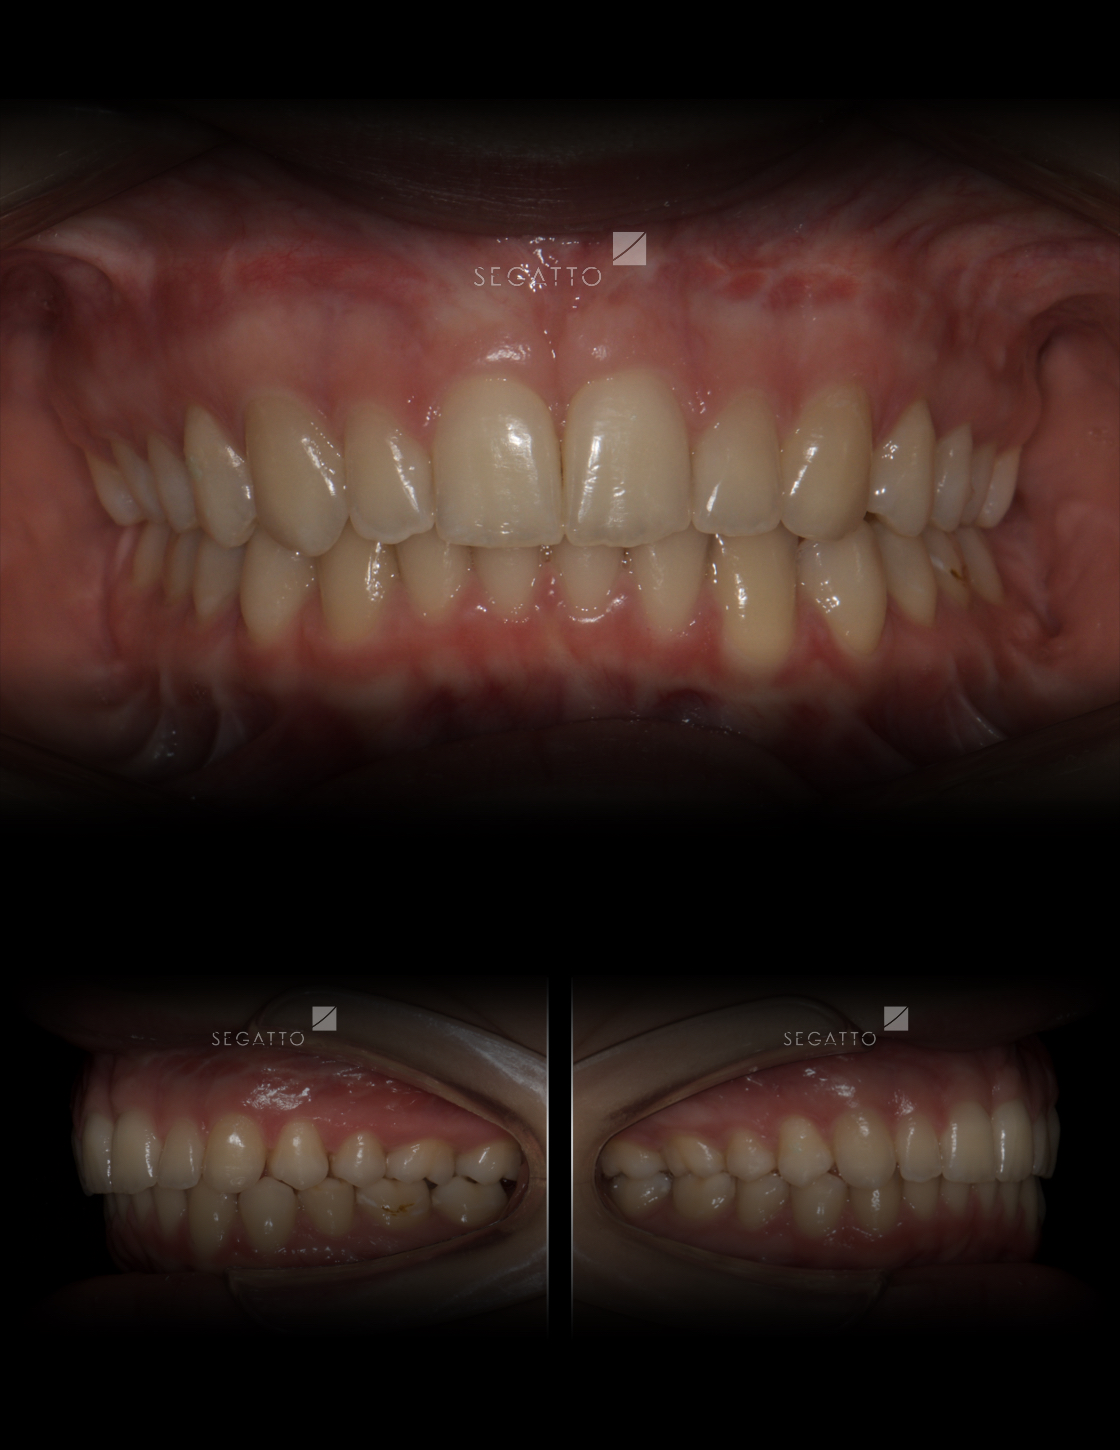

Orthodontics

Cases